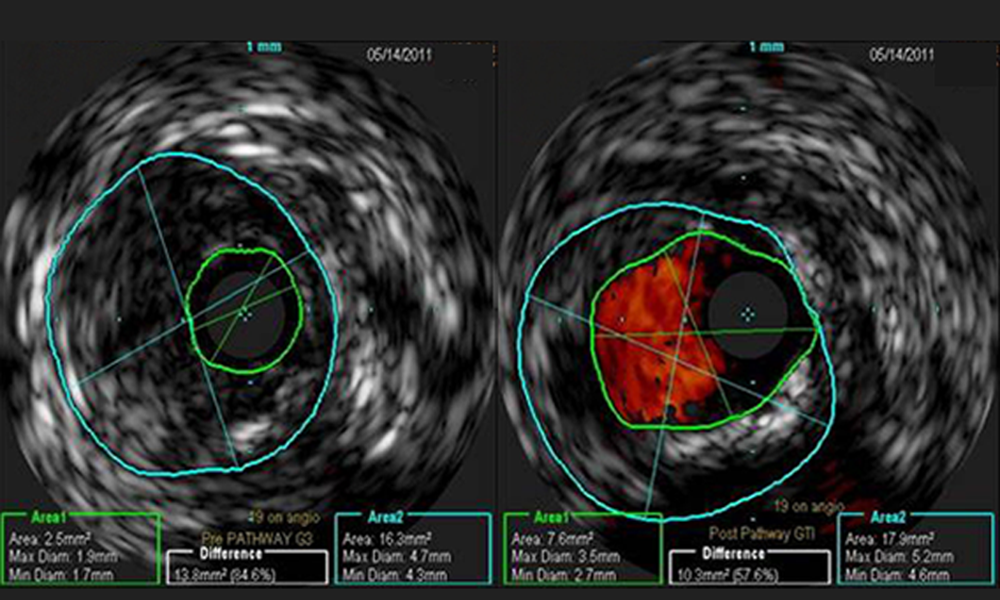

Feb 07, 2016Key Learnings From Jetstream Atherectomy Calcium Study

Insights on removing severe superficial calcium to achieve significant luminal gain in femoropopliteal arteries PDF, 6.0 MB